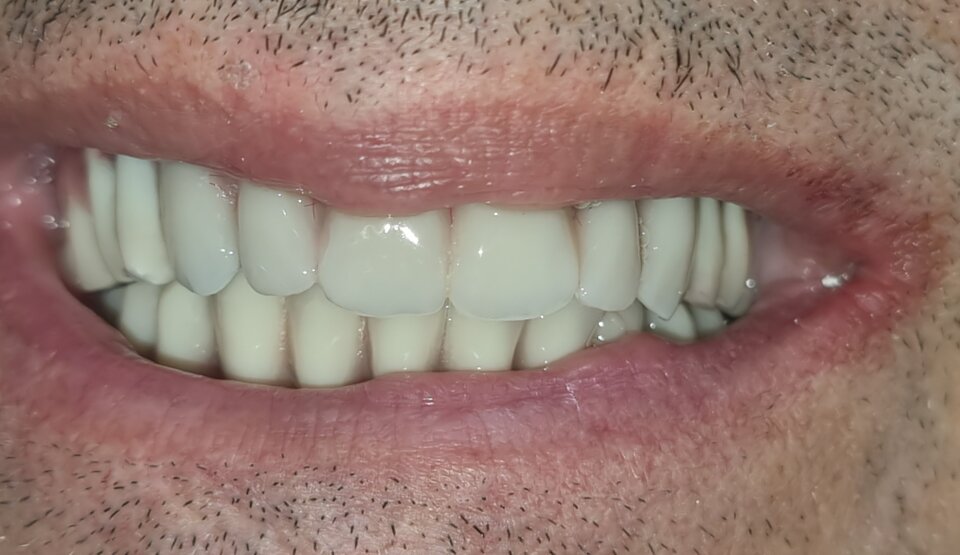

Qualunque sia la tecnica usata il risultato che si vuole ottenere è la riabilitazione della funzione masticatoria con denti fissi.

La tecnica più usata al giorno d'oggi si chiama ALL ON FOUR oppure ALL ON SIX e prevede la realizzazione di una intera arcata composta di dodici ( più raramente quattordici) denti fissi montati su una barra in titanio che verrà fissata su 4 o 6 impianti inseriti nell'osso ( da cui il nome).

QUI SOTTO UN ESEMPIO DI ALL ON FOUR DEFINITIVA A CARICO IMMEDIATO REALIZZATA NELLO STESSO GIORNO